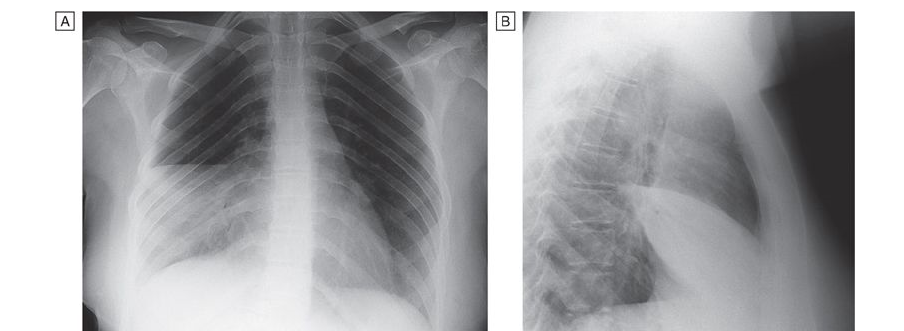

Unfortunately, the sensitivity and specificity of the findings on physical examination are less than ideal, averaging 58% and 67%, respectively. Therefore, chest radiography is often necessary to differentiate CAP from other conditions. Radiographic findings may include risk factors for increased severity (e.g., cavitation or multilobar involvement). Occasionally, radiographic results suggest an etiologic diagnosis. For example, pneumatoceles suggest infection with S. aureus, and an upper-lobe cavitating lesion suggests tuberculosis. CT is rarely necessary but may be of value in a patient with suspected postobstructive pneumonia caused by a tumor or foreign body. For outpatients, the clinical and radiologic assessments are usually all that is done before treatment for CAP is started since most laboratory results are not available soon enough to influence initial management significantly. In certain cases, the availability of rapid point-of-care outpatient diagnostic tests can be very important (e.g., rapid diagnosis of influenza virus infection can prompt specific anti-influenza drug treatment and secondary prevention).

Fever and leukocytosis usually resolve within 2–4 days in otherwise healthy patients with CAP, but physical findings may persist longer. Chest radiographic abnormalities are slowest to resolve and may require 4–12 weeks to clear, with the speed of clearance depending on the patient’s age and underlying lung disease. Patients may be discharged from the hospital once their clinical conditions are stable, with no active medical problems requiring hospital care. The site of residence after discharge (nursing home, home with family, home alone) is an important consideration, particularly for elderly patients. For a patient whose condition is improving and who (if hospitalized) has been discharged, a follow-up radiograph can be done ~4–6 weeks later. If relapse or recurrence is documented, particularly in the same lung segment, the possibility of an underlying neoplasm must be considered.

Clinical improvement, if it occurs, is usually evident within 48–72 h of the initiation of antimicrobial treatment. Because findings on chest radiography often worsen initially during treatment, they are less helpful than clinical criteria as an indicator of clinical response in severe pneumonia. Seriously ill patients with pneumonia often undergo follow-up chest radiography daily, at least until they are being weaned off mechanical ventilation. Once a patient has been extubated and is in stable condition, follow-up radiographs may not be necessary for a few weeks.